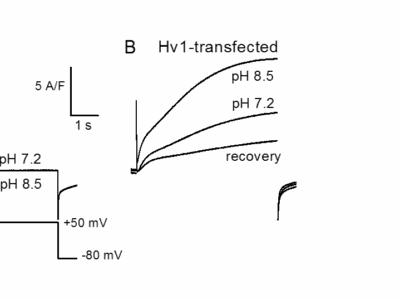

Our research is focused on the physiology and pathophysiology of skeletal muscle function. It aims at understanding how mechanisms involved in the control of skeletal muscle Ca2++ homeostasis and excitation-contraction (EC) coupling operate under normal and disease conditions. For this we use a combination of molecular biology, biochemistry, in vivo gene transfer and simultaneous electrophysiology and fluorescence detection on cultured cells and on single isolated differentiated muscle fibers.

Muscle contraction is initiated when action potentials fired at the end-plate of the muscle cells propagate throughout the plasma membrane and trigger a conformational change of the CaV1.1 protein which gates open a Ca2+release channel (type 1 ryanodine receptor, RyR1) in the sarcoplasmic reticulum (SR) membrane. Ca2+then gets released from the SR into the cytosol and triggers contraction. Besides Ca2+release from the SR there is also Ca2+entry from the extracellular medium.